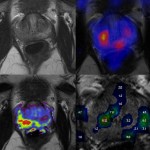

PET/MRI je nejnovější metoda zobrazování na molekulární úrovni, která v sobě spojuje pokročilé systémy magnetické rezonance a pozitronové emisní tomografie. Samotná definice je poněkud komplikovaná. V podstatě se však jedná o spojení velice přesného strukturálního i funkčního zobrazení lidského těla pomocí magnetické rezonance se zobrazením látkové přeměny tkání pozitronovou emisní tomografií. Pro zobrazení látkové přeměny se používají radionuklidem označené látky, obvykle velice podobné látkám vlastním lidskému tělu, nejčastěji palivu energetického systému tkání, tedy hroznovému cukru – glukóze. PET/MRI pomůže odlišit strukturální změny lidských orgánů a přesně posoudit změny jejich životních projevů. Obě metody zobrazení MRI a PET je tak možné nyní používat současně a zobrazení získávat najednou.

Samotná konstrukce přístroje je velice originální technické řešení. Uvnitř tunelu magnetické rezonance je uložen ještě detektorový prstenec pro pozitronovou emisní tomografii. Jednoduchý popis ale v sobě skrývá velice složité vyřešení problémů nového způsobu zpracování obrazu, protože v extrémně silném magnetickém poli již neplatí běžné principy částicové fyziky ani elektrotechniky.

Výhod zobrazení je hned několik. Nejvýznamnější je podstatné snížení radiační zátěže u některých skupin onkologicky nemocných, u nichž jsou prováděna opakovaná vyšetření při stanovení diagnózy, rozsahu onemocnění a pak při kontrole účinku léčby či sledování po jejím ukončení. Jsou to především nemocní s lymfomy nebo s nádory varlete. Významné je ovlivnění nastřádané dávky také u dětských nemocných. Úzce spolupracujeme kromě pracovišť Fakultní nemocnice v Plzni také s Klinickou dětské onkologie FN Motol a právě u dětských onkologických nemocných jde o podstatnou výhodu PET/MRI. Další výhodou je spojení vysoce kvalitního zobrazení tkání magnetickou rezonancím s metabolickým obrazem u nemocných, kdy se dosud používala často kombinace zobrazení pomocí PET/CT a MRI. PET/MRI zjednoduší předoperační zobrazení rozsahu a chování nádorů mozku nebo dutiny ústní, ale i přesné předoperační posouzení rozsahu postižení prsu karcinomem spolu s možností posouzení, zda nejsou přítomny metastázy. Nesmím opomenout ani výhody v zobrazování pánevních nádorových onemocnění – nádorů dělohy nebo konečníku a zejména karcinomu prostaty. Jak je zřejmé, hodnocení PET/MRI klade na lékaře mimořádné nároky, my při práci s novým zařízením zúročíme svoje dvacetileté zkušenosti s MRI a desetileté zkušenosti s PET/CT.

Zeptali jste se na velice významný aspekt moderního zobrazování. Lze použít příměr porovnání nehybridních metod MRI a CT vyšetření. CT zůstává suverénní metodou pro hodnocení plicní tkáně a některých dalších orgánů jako jsou slinivka břišní nebo cévního zásobení jater či ledvin. V onkologických indikacích jako jsou posuzování plic postižených nádorovým procesem, hodnocení nádorů slinivky břišní, plánování moderních technik operace nádorů ledvin, ale i třeba u hodnocení účinků léčby nádorů vaječníku zůstane PET/CT základní metodou volby. Z nenádorových indikací bude stále výhodnou indikací PET/CT hledání původu horečnatých onemocnění a sepse. Toto jsou indikace, ve kterých budeme využívat náš nový špičkový hybridní tomograf PET/CT, v létě 2014 nahradil starší zařízení používané téměř deset let.

Existují dvě oblasti, ve které se PET/MRI nabízí jako velice efektivní. Jsou to neurologické indikace zejména včasné odhalení Alzheimerovy nemoci, dále vyhledávání ložisek, která vyvolávají epilepsii. PET/MRI bude přínosem i pro diagnostiku onemocnění srdečního svalu, například hodnocení životaschopnosti tkáně u nemocných s ischemickou chorobou srdeční. I zde je výhodou kombinovat posouzení metabolismu s hodnocením struktury tkáně magnetickou rezonancí.